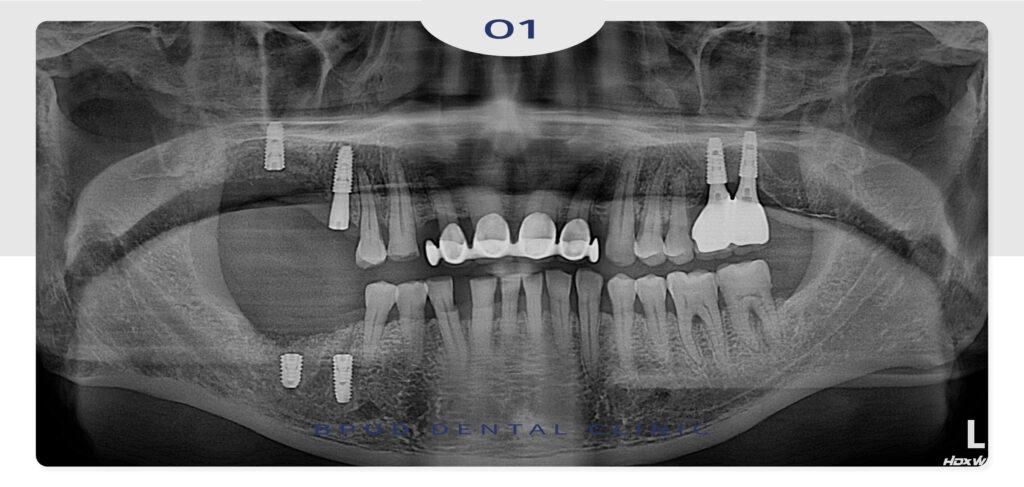

오늘은 심한 골소실로 인해 발치 후

뼈이식 임플란트를 진행하신 환자분을

소개해 드리도록 하겠습니다.

환자분께서는 흔들리는 치아를 오랫동안

방치하여 염증이 진행되다 골 소실이 심하게

진행되고 있었는데요.

먼저 위, 아래 심한 염증이 진행되고 있는

원인 치아들을 발치하고 위쪽은 상악동 거상술,

아래쪽에는 뼈이식을 통해 임플란트 식립을

진행하는 것으로 계획을 수립하였습니다.